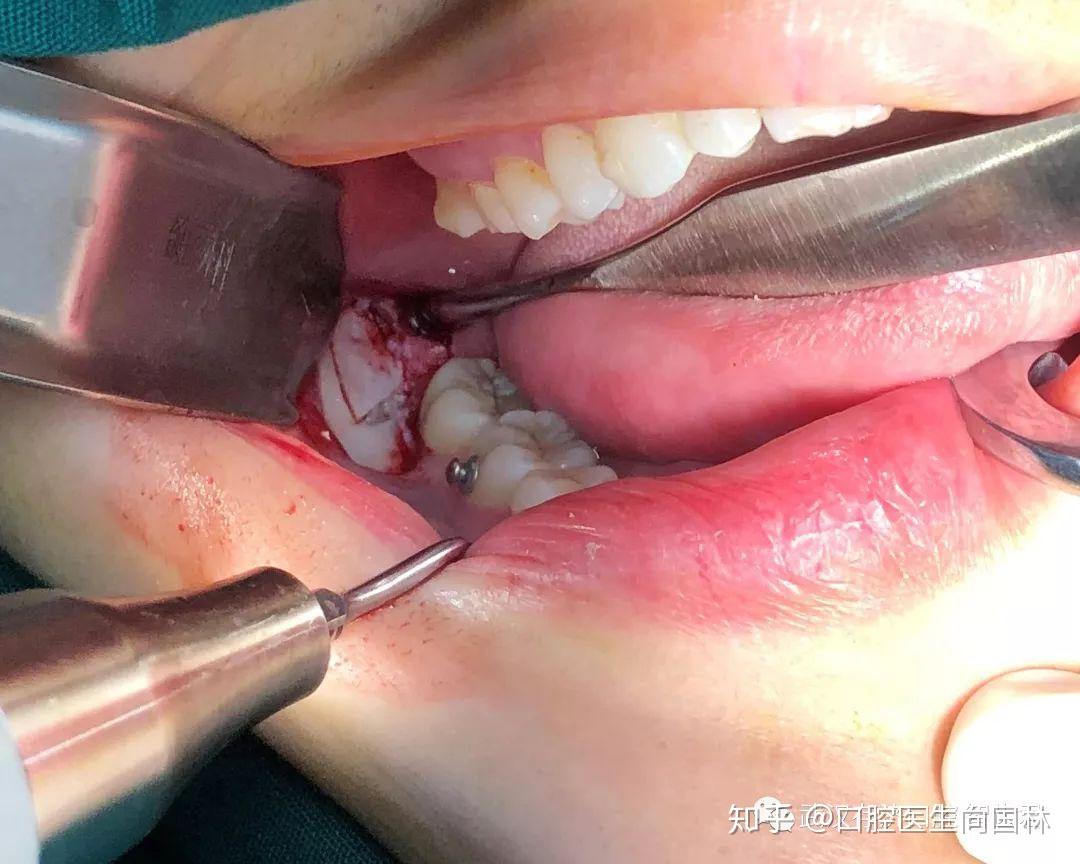

真实案例超声骨刀微创拔除下颌阻生智齿